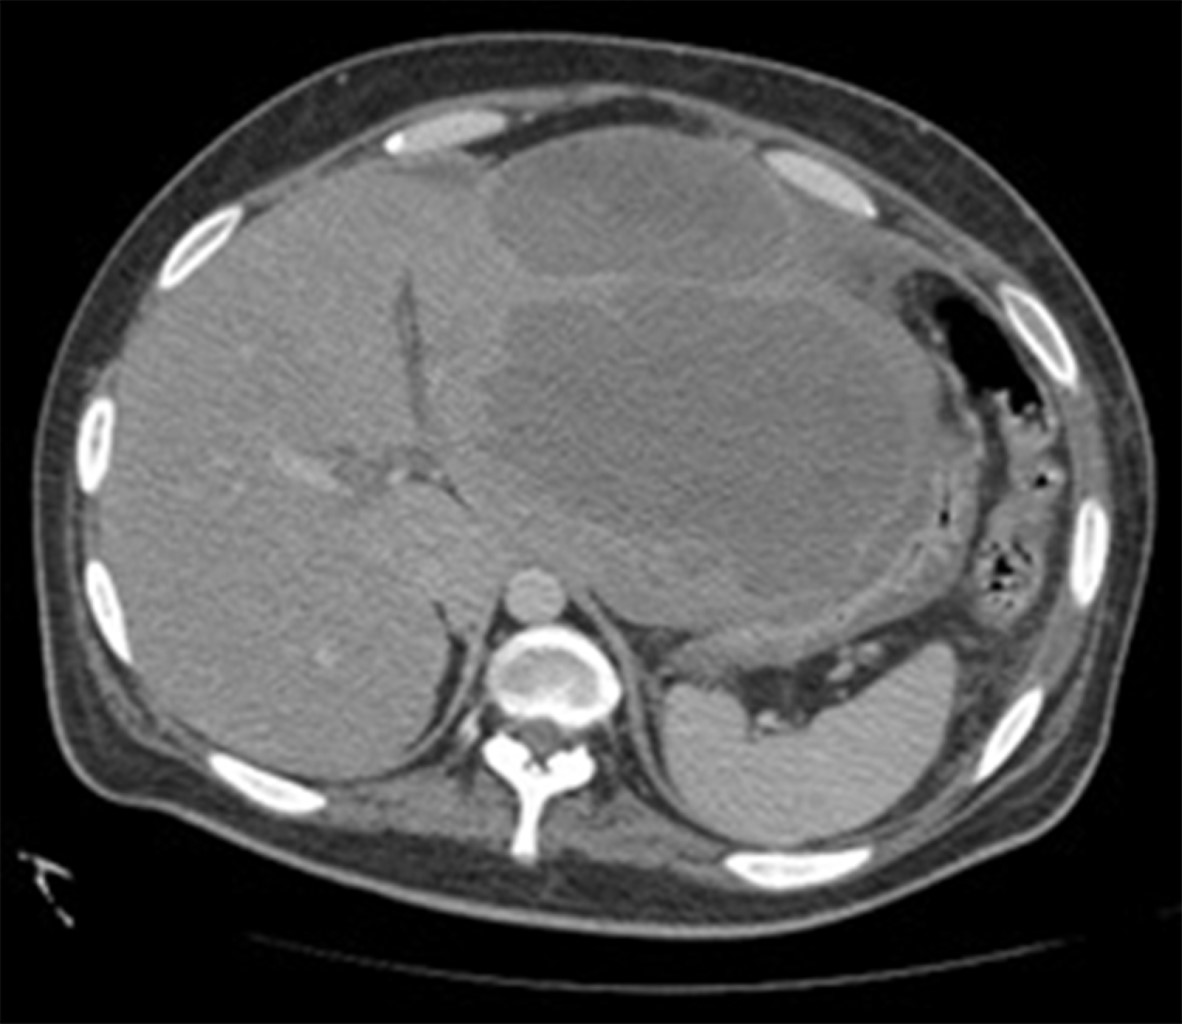

An anteroposterior (AP) chest X-ray was performed, in which a left pleural effusion covering more than 50% was visualized. A computed tomography scan showed a significant amount of fluid in the left pleural space that conditioned a passive atelectasis of the lower lobe (Figure 1); the liver was found with heterogeneous density with an increase of the left hepatic lobe secondary to the presence of a heterogeneous hypodense lesion with lobulated borders, showing peripheral reinforcement and some internal septa covering segments II, III, IVa, and IVb measuring approximately 20 × 14.5 × 12.5 cm (Figure 2), conditioning posterior displacement and compression of the stomach and pancreas and caudal displacement of the intestinal loops (Figures 3 and 4). In the lower pole of the right hepatic lobe adjacent to segment IV, a homogeneous cystic lesion with peripheral enhancement was identified after intravenous contrast administration, measuring 25 × 27 × 13 cm in its major axes. A Foley tube and nasogastric tube were placed as initial management draining a liquid of gastric characteristics (30 ml). A central catheter was placed and verified by radiography. Imaging studies were requested. Fasting was ordered and fluid therapy, antibiotic therapy with ceftriaxone and metronidazole, pain management, glycemic control, and gastric protection were started. When visualizing the image of the left pleural effusion, it was decided to perform a thoracentesis, obtaining a thick exudate with a chocolate appearance. When the tomography was available, urgent surgical treatment was performed.

Figure 3